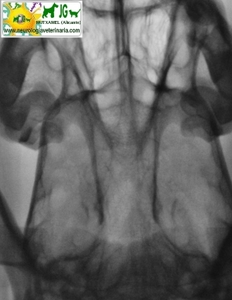

Radiografía digital (no digitalizada) de un cocker inglés mostrando el diente del axis. |